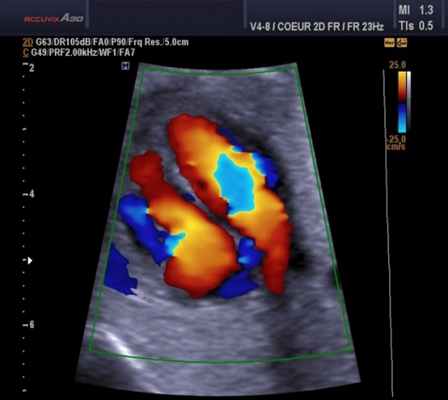

Цветовой допплер (Color Doppler). Цветовой допплер - аналог импульсного допплера, где направление и скорость кровотока картируется различным цветом. Так кровоток к датчику принято картировать красным цветом, от датчика - синим цветом. Турбулентный кровоток картируется сине-зелено-желтым цветом.

Для облегчения выявления турбулентного движения (завихрений) существует порог скорости, выше которого происходит изменение цвета (во многих аппаратах это зелены). «Мозаичный» узор на участке турбулентного потока позволяет легко установить регургитацию (смену направления движения), что помогает определить степень недостаточности клапанов.